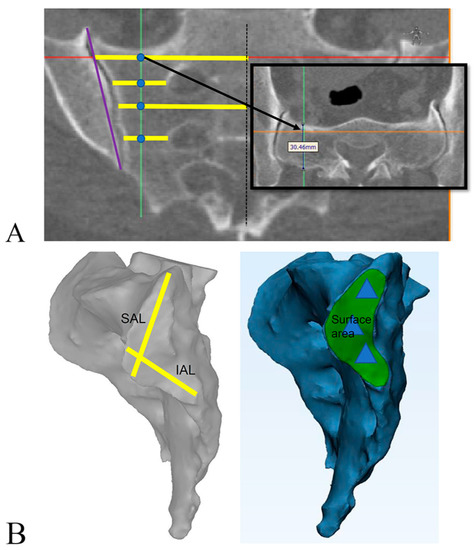

Measured through multiplanar reconstructions parallel to the S1 body

| Superior articular limb | 28.4 mm | Distance across inscribed diameters of two implants. Two implants are typically placed in the superior limb of the SIJ. |

| Inferior articular limb | 28.4 mm | Distance across inscribed diameters of two implants. Two implants are typically placed in the inferior limb of the SIJ. Note that second implant is in both limbs. |

| Surface area | 3 × π*r2 = 475 mm2 | Cross-sectional area of circles formed by three implants. |

| SIJ height | 42.6 mm | Total length of three diameters of implants. |

| AP thickness of the sacral ala | 14.2 mm | The AP thickness should be larger than the inscribed diameter of the implant; otherwise, the implant protrudes from the sacrum. |